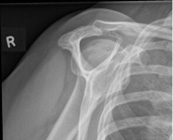

Plain Films: Three different views of the shoulder are typically used to evaluate shoulder pathology: anterior-posterior view (Grashey view), axillary lateral view, and the outlet view. In the setting of SLAP tears, plain films are helping for assessing for any other shoulder pathology thay may be present.

Image 6 [9]. AP view of the shoulder (“Grashey” view).

Image 8 [11]. Shoulder outlet view.